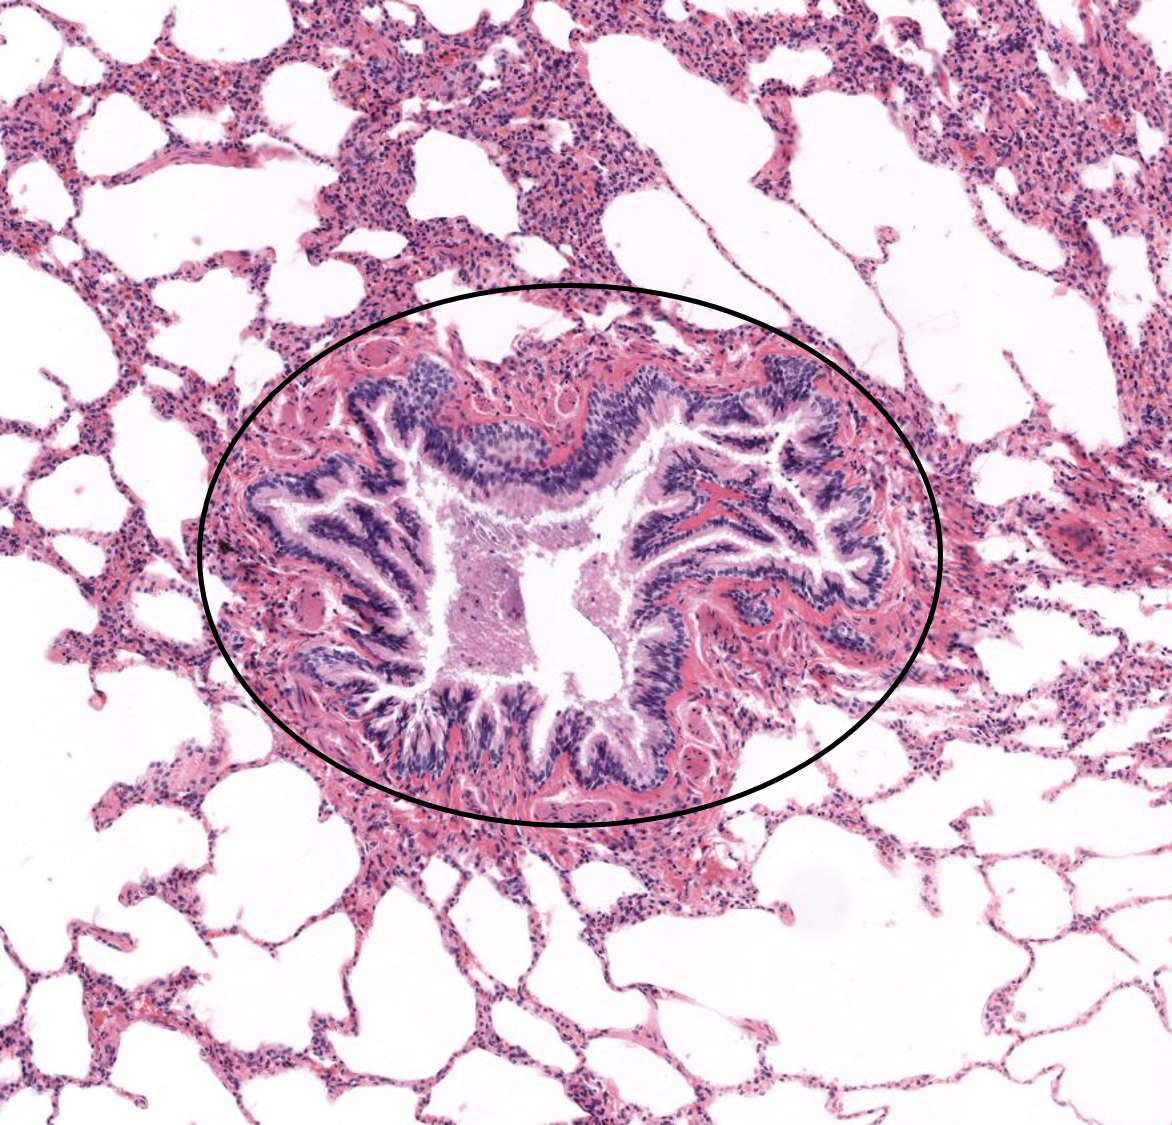

Trompa uterina

1: Trompa uterina - mucosa

2: Camada muscular - músculo liso